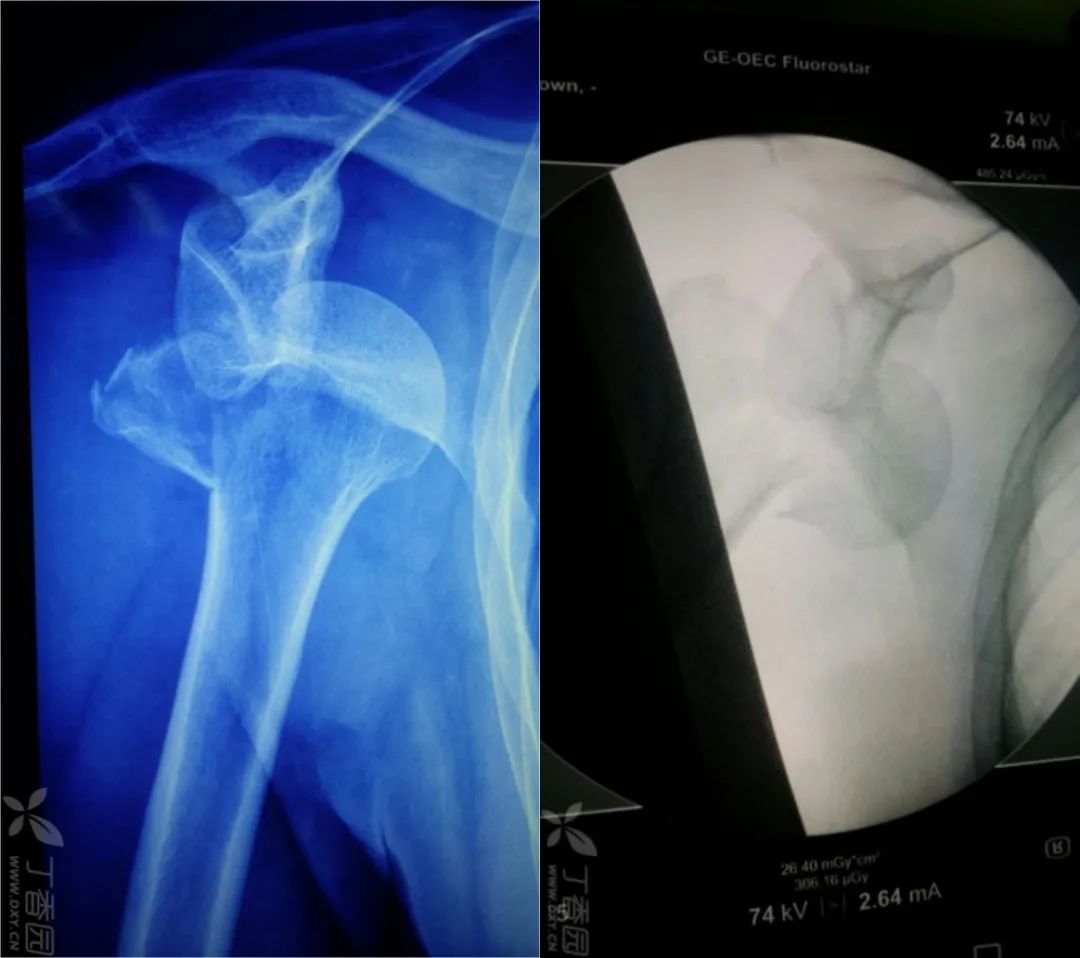

都这么简单吗?还真不一定,如果让你遇到了肩关节脱位合并隐匿性骨折就是一个巨大的坑了。看看下面的病例:

看片子似乎是一个简单的肩关节脱位并大结节撕脱骨折。

整复后拍片复查却成这个样子了……

其实这种往往都是合并了肱骨颈部隐匿性骨折。

临床上还真不罕见,只要遇到一例绝对让你头大如斗,因为骨折移位合并脱位处理起来极为麻烦,一般都预后欠佳。